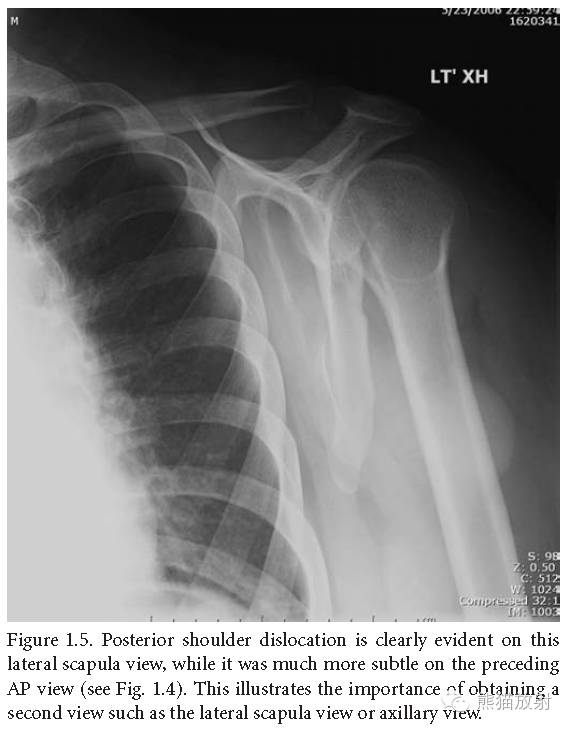

肩关节后脱位:在肩胛骨侧位片上显示的更为明显,检查时多个体位(侧位、腋位)很重要。